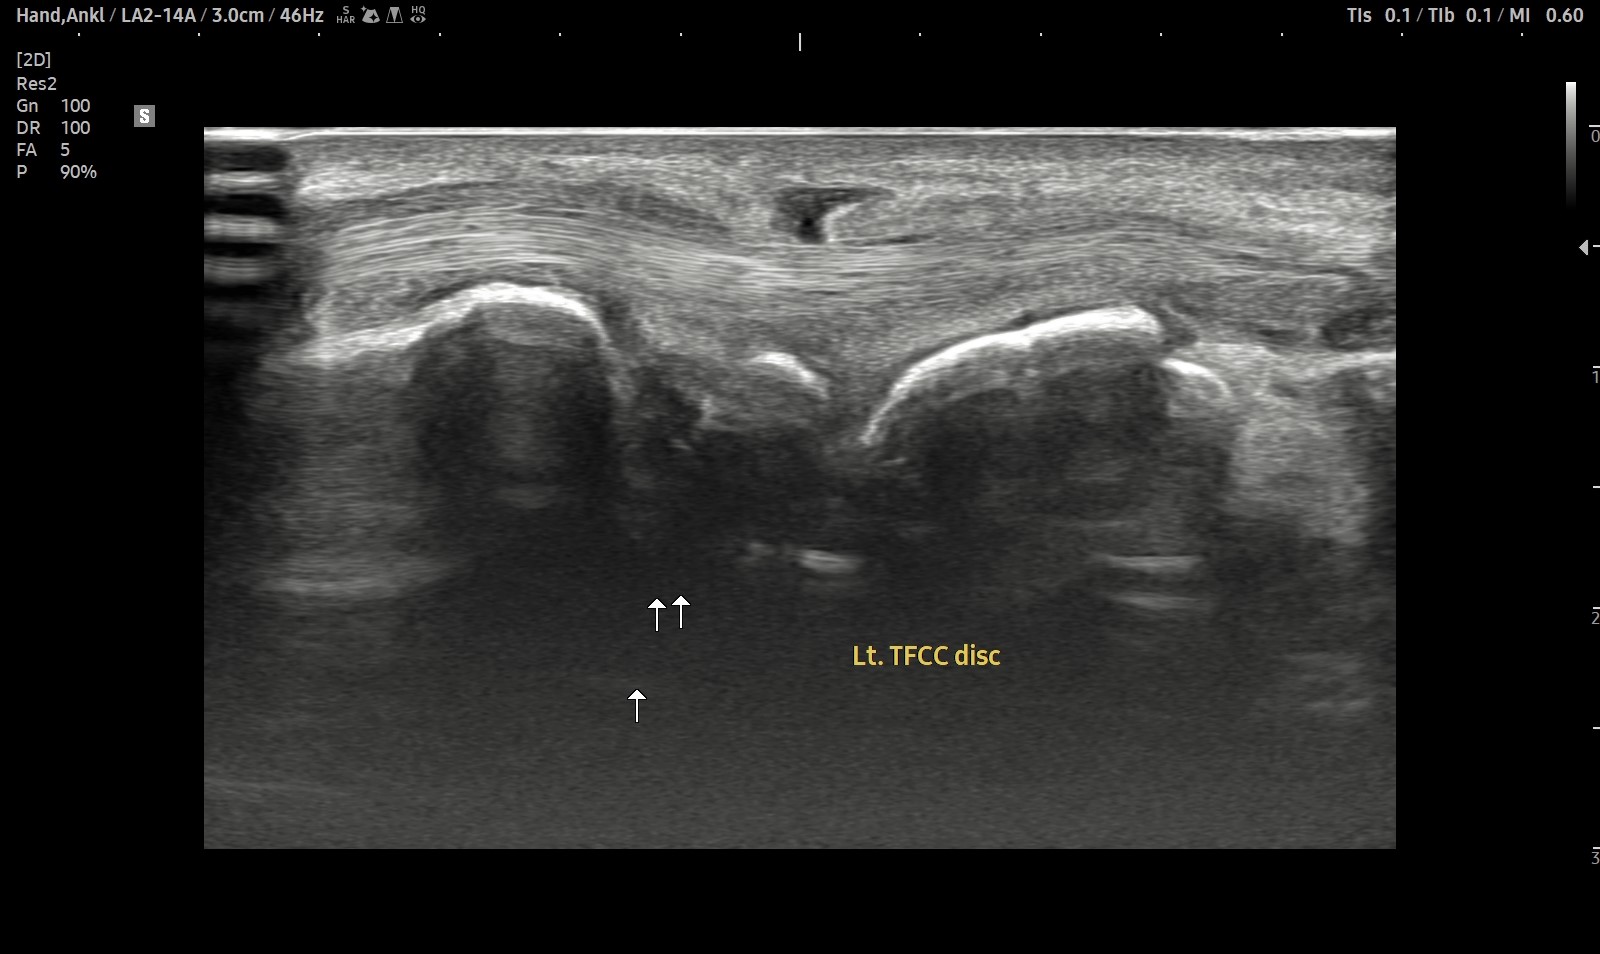

- 치료기간 : 2025 . 2 . 22 ~ 2025. 9 . 20

- 치료횟수 : 4cycle (20회)

8cycle 계획에서 빠른 호전으로 조기 치료 종결 case.

치료 전

치료 후